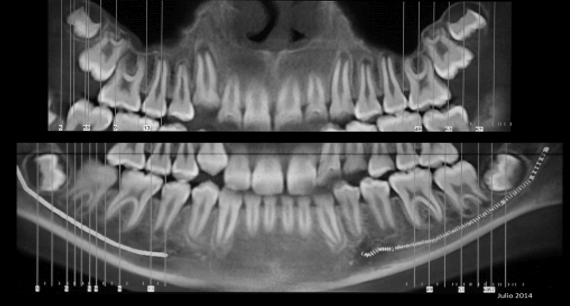

Radiografía Panorámica Inicial

Se puede evidenciar la elongación del cóndilo mandibular izquierdo